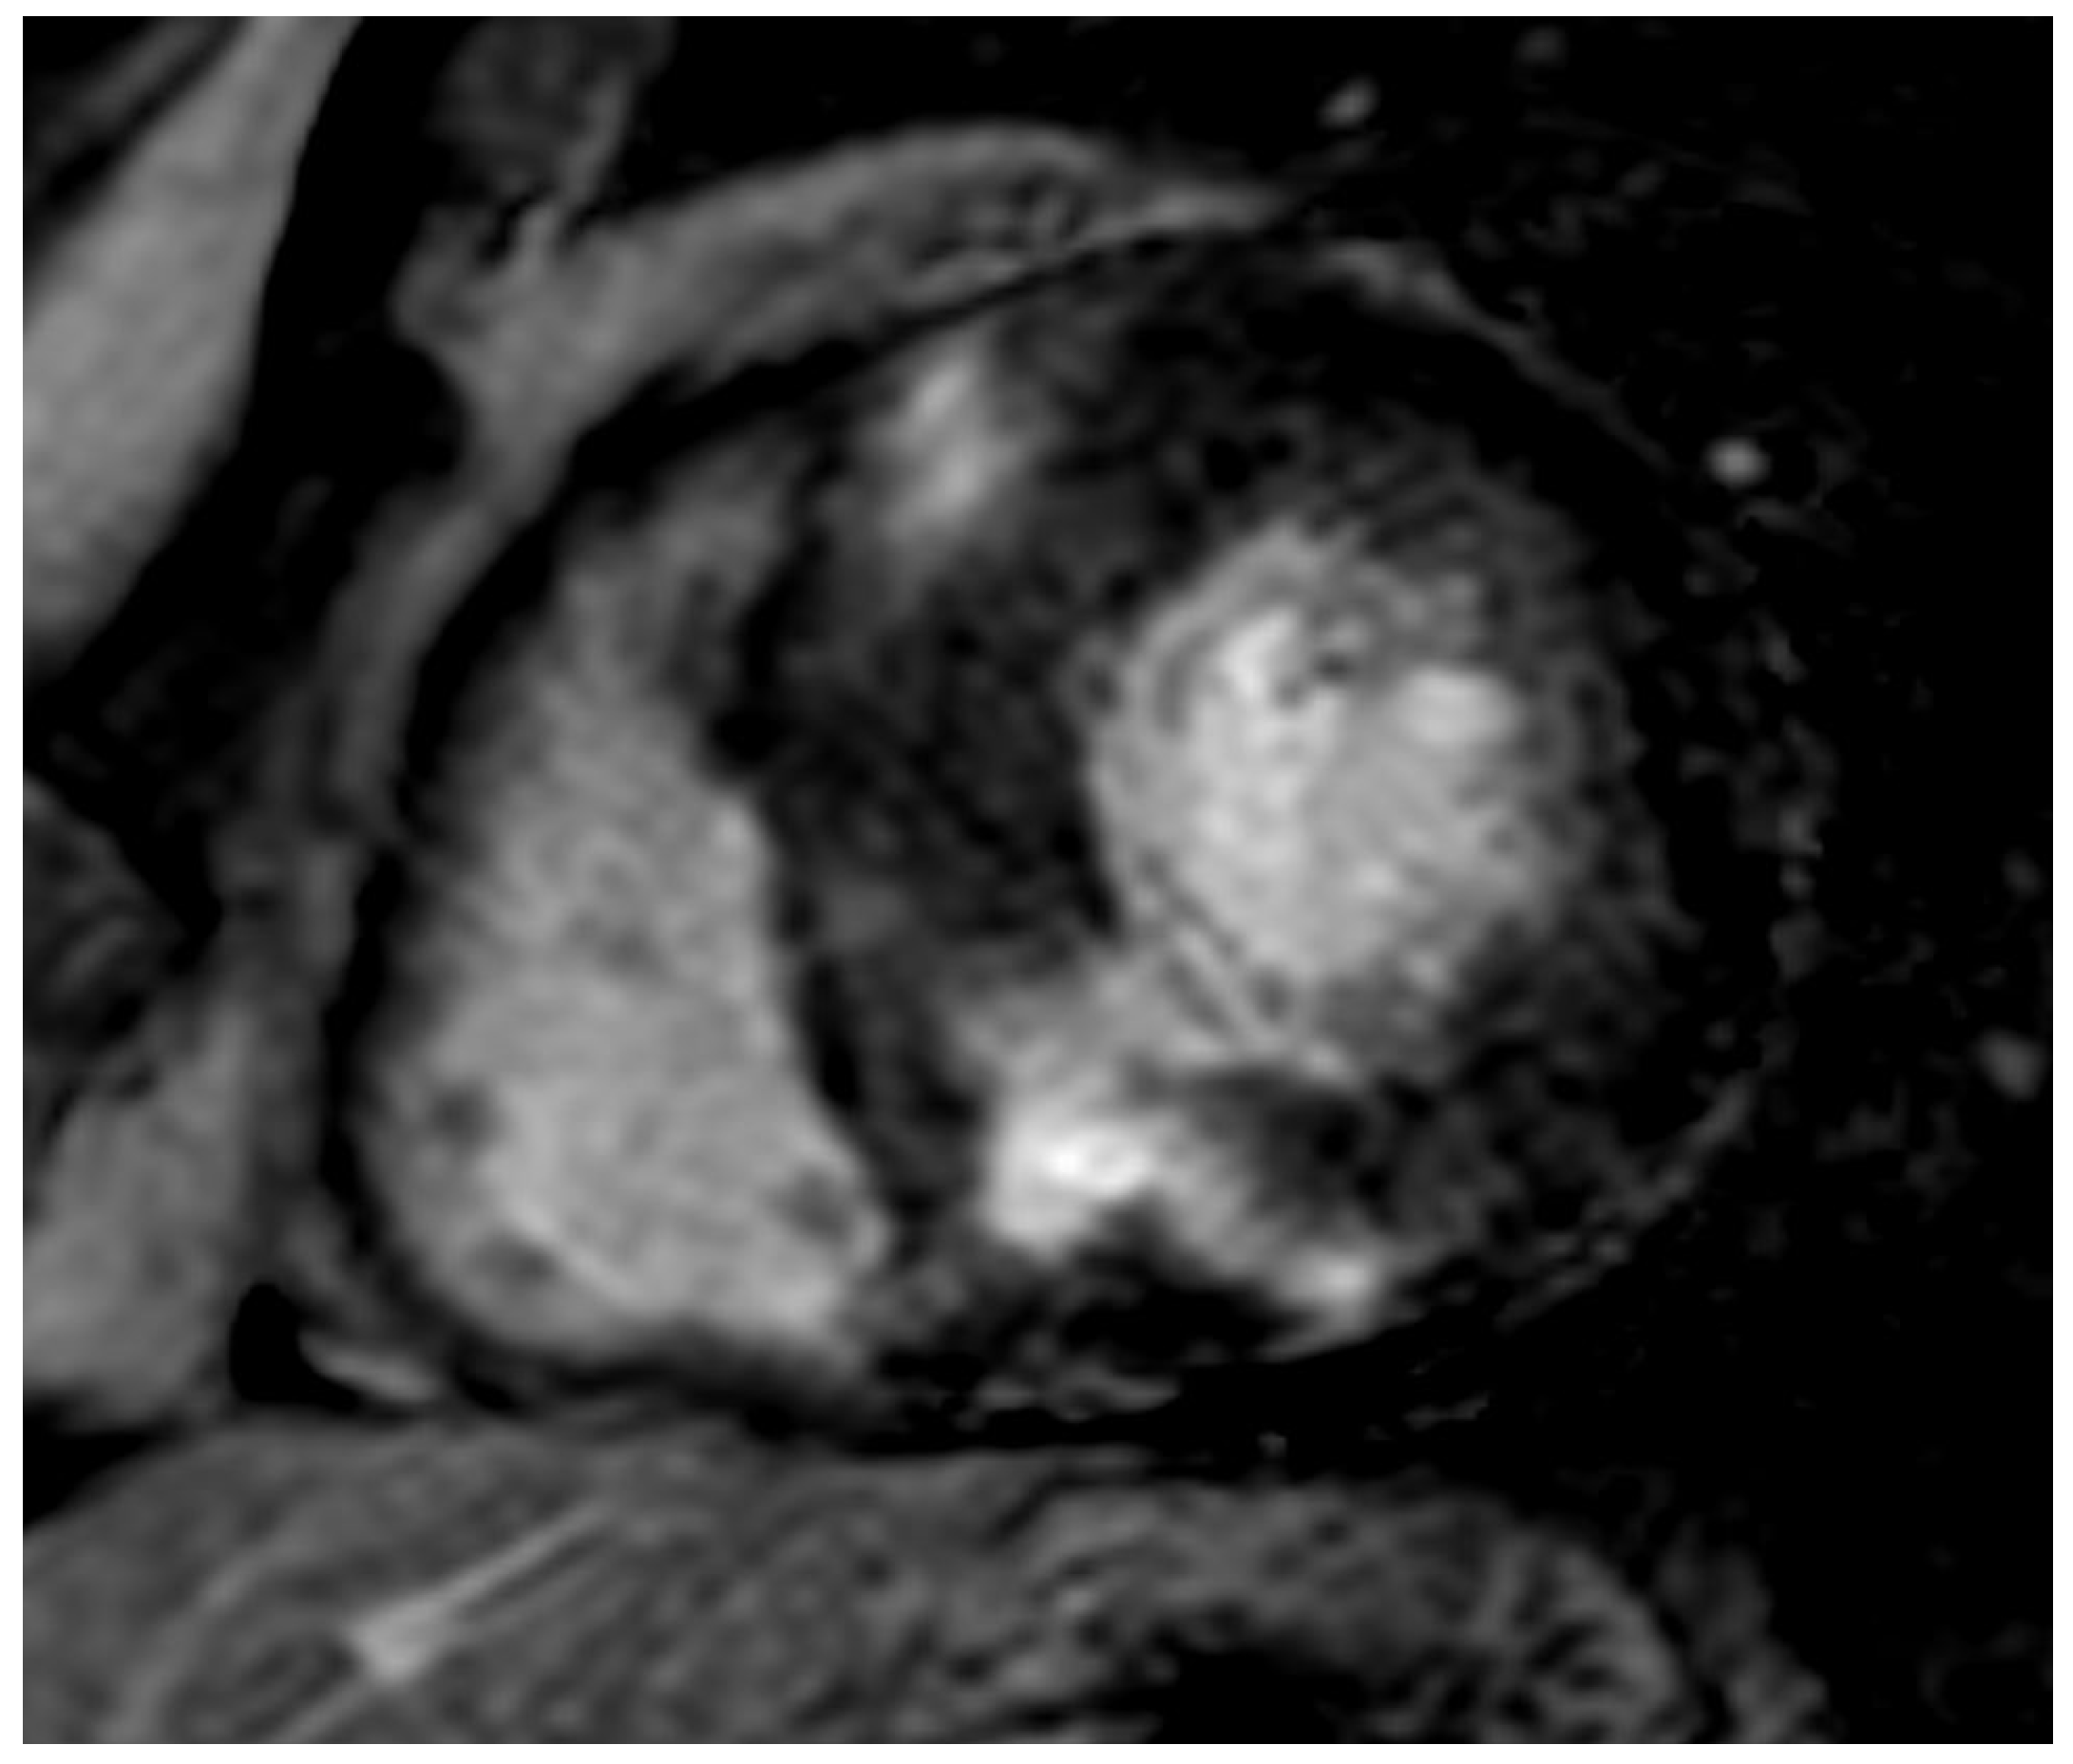

Figure 5.

AL 64-year-old patient diagnosed with endomyocardial biopsy. PSIR sequence highlights transmural patchy LGE pattern.